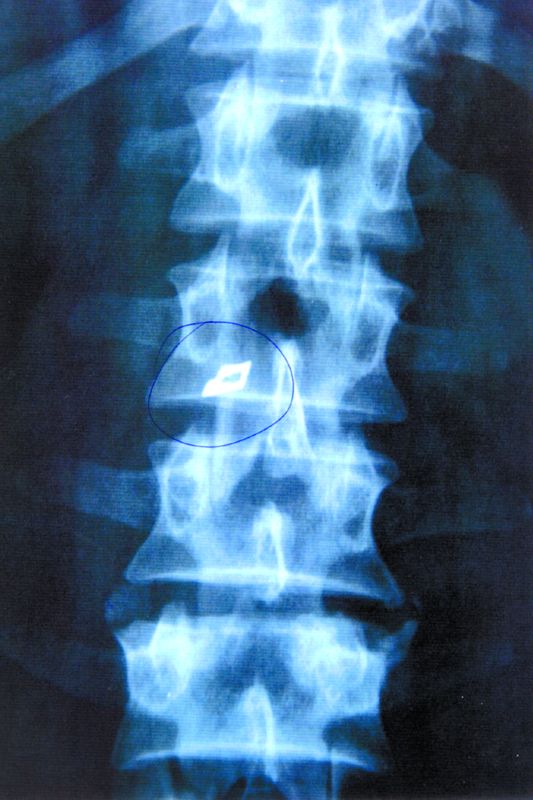

Ajunsese să fie încălţat de soţie şi se plângea mereu de dureri de spate, deşi, aparent, nu ar fi avut motive. La o radiografie, Ionel Nistor, din Oradea, a descoperit cauza suferinţei sale: un vârf de bisturiu uitat de dr. Ştefan Florian Ion, în timpul unei operaţii efectuate cu trei ani înainte.

Cu dovada în mână, Nistor a mers să-i ceară socoteală doctorului. “Când a văzut pentru ce am venit, neurochirurgul s-a înroşit la faţă şi mi-a spus senin că nu e decât un fragment care se poate scoate, iar dacă nu sunt mulţumit să îl dau în judecată”, îşi aminteşte bărbatul.

Neîncrezător în serviciile medicale de la Cluj-Napoca, orădeanul s-a operat la Spitalul Elias, din Capitală, unde i-a fost scoasă lama din coloană. “Am rămas uimit de dimensiunea ei: cam patru cm lungime!”, mai

spune Nistor. Întors acasă, acesta a încercat să-şi facă dreptate. În timp ce cadrele medicale din Cluj l-au scos basma curată pe doctorul Florian, Colegiul Medicilor din România i-a dat o mustrare.

“După extragerea fragmentelor s-a efectuat imediat, intraoperator, radioscopia plăgii, pentru a depista eventuale resturi desprinse din lama de bisturiu, însă nu a fost identificat nici un corp străin”, susţine doctorul Florian într-o înştiinţare adresată Tribunalului Cluj. Momentan, bărbatul, suferind de mai multe boli, a primit verdict de handicap accentuat. “Vreau despăgubiri pentru cei trei ani de chinuri în care am purtat moartea în spate”, e dorinţa lui Ionel Nistor.